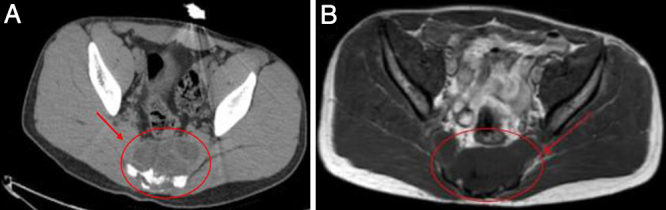

Observations: A 17-year-old male with a history of HC disease presented with low back pain radiating to both lower limbs, claudication, and chronic constipation for 5 years. Imaging revealed a large, multiloculated sacral cyst extending retrorectally and presacrally from S3 to S5, involving the spinal canal, compressing the rectum, and causing sacral erosion. A diagnosis of sacral hydatidosis was made, and the patient was started on albendazole, with surgical excision planned.